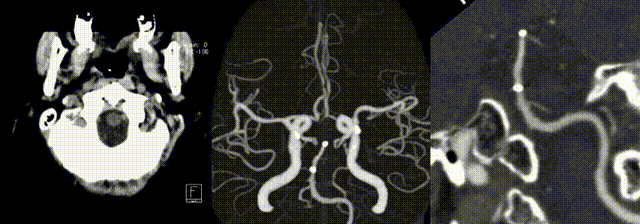

Postoperative Angiography

Postoperative CTA confirmed patency of the stented segment